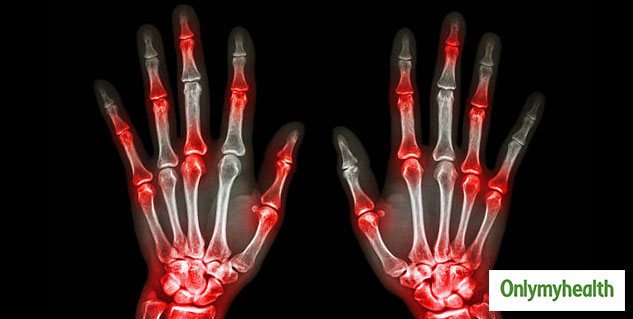

आर्थराइटिस न केवल जोड़ों को प्रभावित करता है बल्कि आपके दिल की सेहत को भी प्रभावित करता है। ये हम नहीं बल्कि हाल ही में आया शोध बता रहा है। दरअसल जर्नल एनल्स ऑफ द रयूमैटिक डिजीज में प्रकाशित एक अध्ययन की मानें, तो गठिया, विशेष रूप से संधिशोथ (आरए) और सोरियाटिक गठिया जैसे गंभीर स्थितियों वाले लोगों को दिल का दौरा, स्ट्रोक, अनियमित दिल की धड़कन, उच्च रक्तचाप, दिल की विफलता और एथेरोस्क्लेरोसिस के लिए खतरा बढ़ जाता है। ऐसा इसलिए है क्योंकि हड्डियों की सूजन जहां से भी गुजरती है, हृदय रोग के लिए एक जोखिम कारक बन जाती है।

जर्नल एनल्स ऑफ द रयूमैटिक डिजीज में प्रकाशित एक अध्ययन से यह भी पता चला है कि जोड़ों में दर्द के शुरुआती लक्षणों का इलाज करने के लिए इस्तेमाल की जाने वाली दवाओं से संवहनी कठोरता में सुधार करने में मदद मिल सकती है। दरअसल हड्डियों का सूजन बड़ी धमनियों में लोच का नुकसान करता है और ये बढ़ते हुए हृदय रोग का एक संकेत है। इसलिए, अगर किसी को गठिया है, तो अपने जोड़ों की सुरक्षा के लिए स्थिति को नियंत्रण में रखना महत्वपूर्ण है नहीं तो ये हृदय रोग के विकास के जोखिम को बढ़ा सकता है।

शोध बताते हैं कि जोड़ों के दर्द को प्रबंधित करने के अलावा, गठिया की कुछ दवाएं आपके दिल के स्वास्थ्य को भी बेहतर करने में भी मदद कर सकती हैं। अध्ययन के लिए, शोधकर्ताओं ने 82 रुमेटीइड गठिया रोगियों के विस्तृत एमआरआई दिल के स्कैन किए, जिनमें कोई भी ज्ञात हृदय समस्या नहीं है। उन्होंने संधिशोथ के शुरुआती चरणों में मुख्य धमनी में संवहनी कठोरता (vascular stiffness) की उपस्थिति देखी। बाएं वेंट्रिकल की दीवार (हृदय का मुख्य पंपिंग चैंबर) में कार्डियक स्कारिंग और परिवर्तन के सबूत भी थे। इन निष्कर्षों के आधार पर, शोधकर्ताओं ने सुझाव दिया कि आरए को ठीक करना दिल की बीमारियों से भी आपको ठीक रख सकता है।

आरए दवाओं के साथ एक वर्ष के उपचार के बाद, शोधकर्ताओं ने फिर से स्कैन किया और संवहनी कठोरता में सुधार पाया। अध्ययन के लेखकों ने कहा कि आरए उपचार ने व्यसकुलर स्टीफनेस में सुधार किया। ये निष्कर्ष आरए के शुरुआती उपचार के महत्व को उजागर करते हैं जिससे हृदय रोग (सीवीडी) विकसित होने का खतरा भी कम होता है।